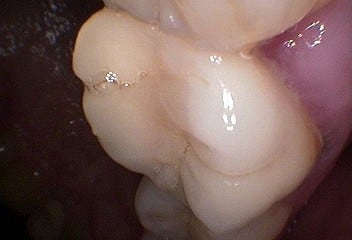

D'autres photos:

Patient 8 qsxfa6 - Eugenol

Patient 9 kmkpcy - Eugenol

Patient 1 naxbfx - Eugenol

Patient 10 osyvpe - Eugenol

et retouchées:

Patient 8 dhkiyd - Eugenol

Patient 9 rlzvzy - Eugenol

Patient 1 w3prxq - Eugenol

Patient 10 athrpl - Eugenol